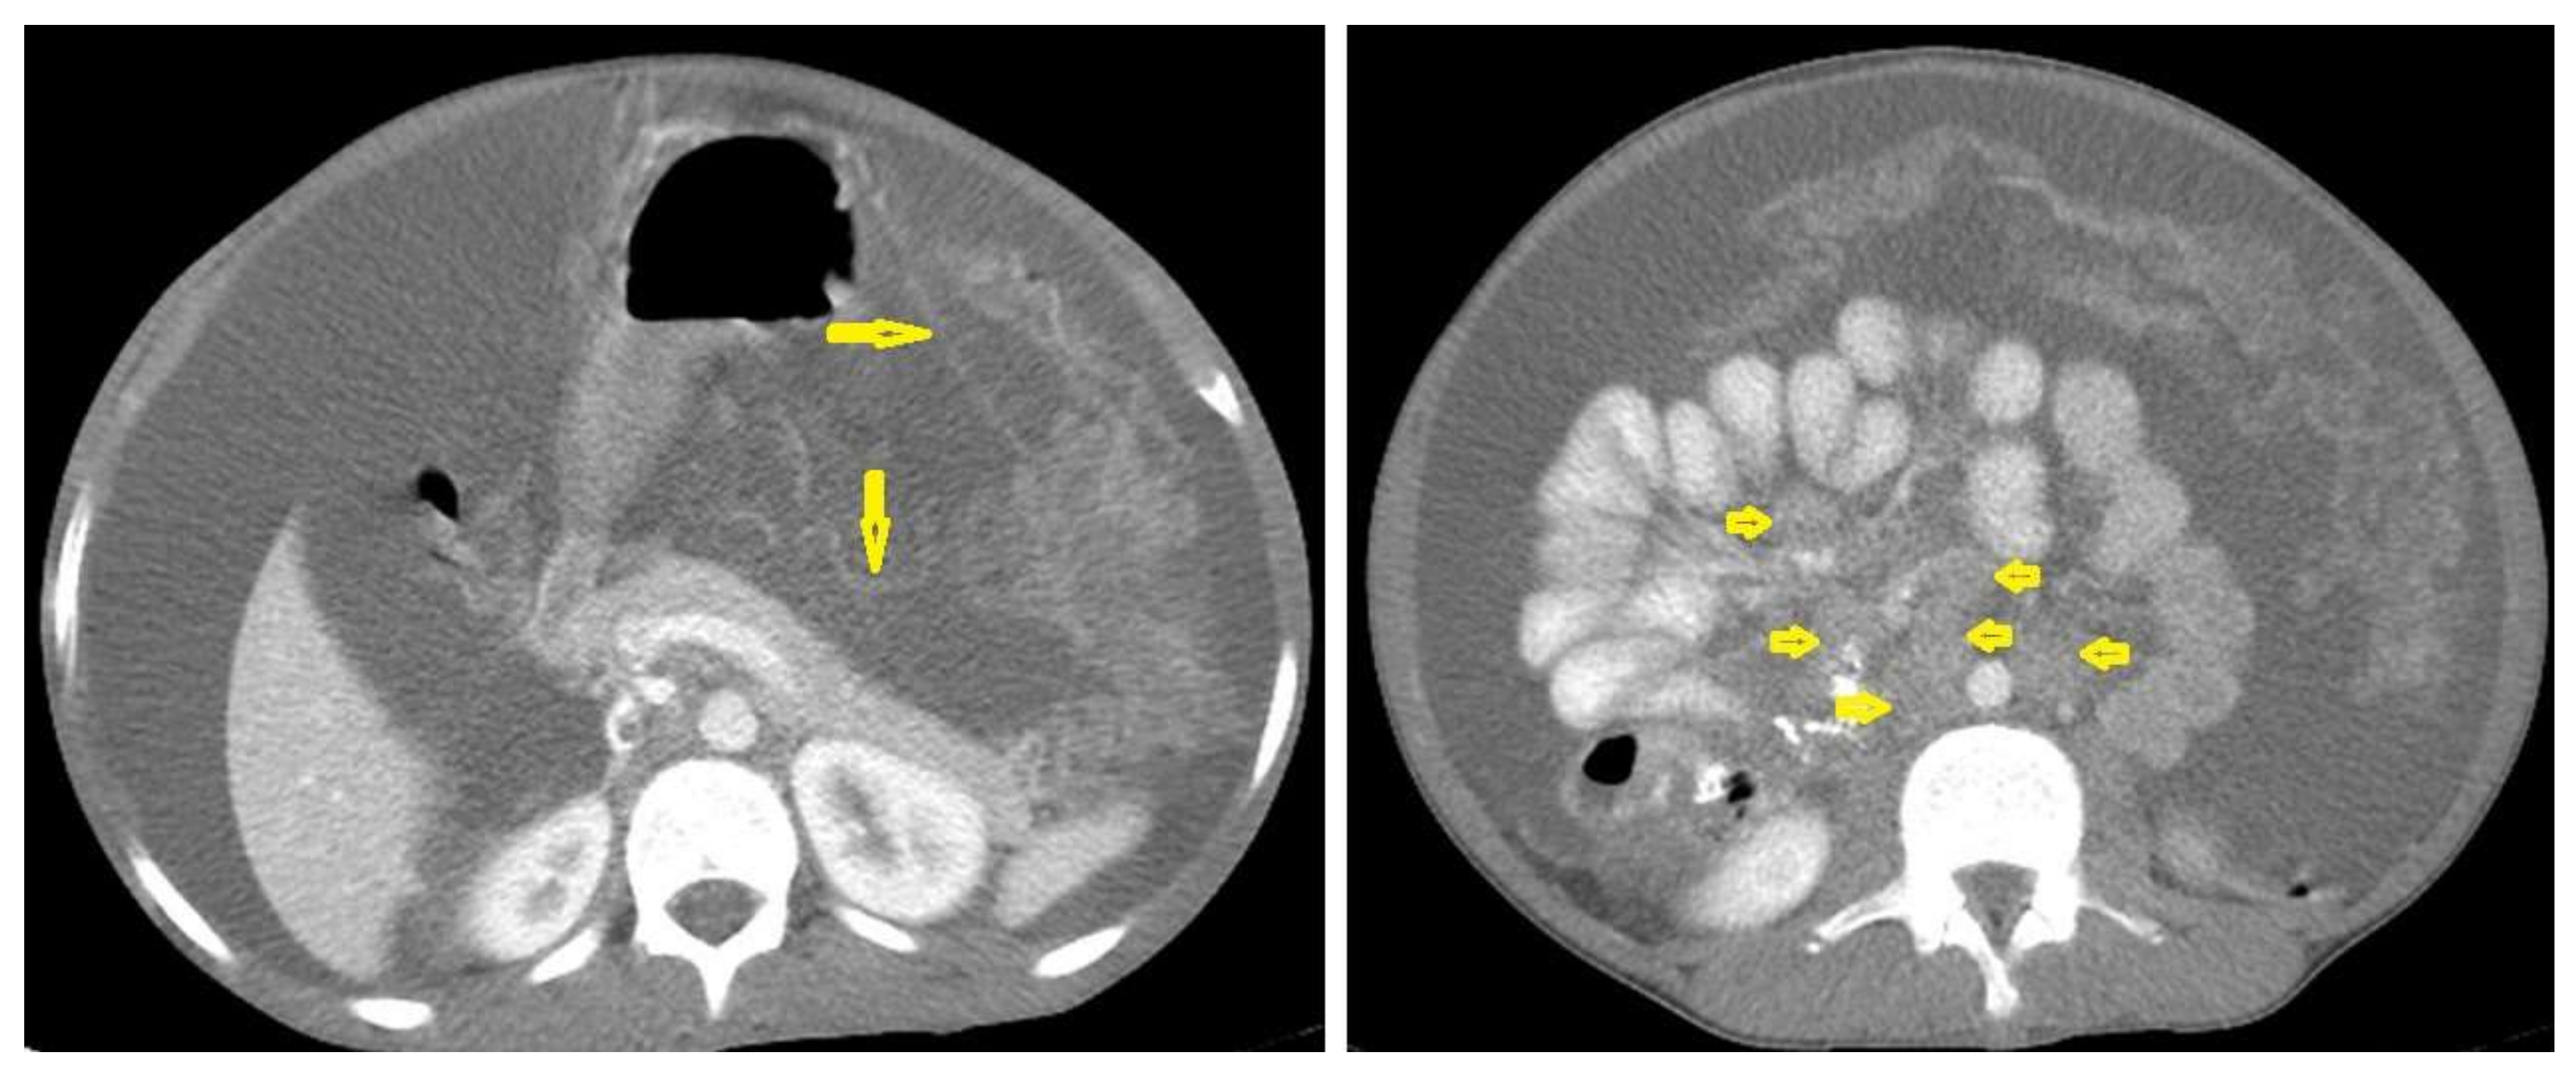

• Tuberculous lymphadenitis (Figure 20) is one of the most common radiological manifestation of abdominal TB which frequently involves multiple groups such as mesenteric and upper paraortic LNs. The majority of patients have enlarged lymph nodes with a low-attenuation center and peripheral-enhancing rim, which is characteristic of TB [45,46]. LNs may show peripheral rim enhancement, inhomogeneous, homogeneous, or no enhancement after contrast administration. Other patterns of LNs include conglomerate LNs with areas of necrosis, more than three enlarged or normal homogenous LNs in one section, or calcified LNs [45]. TB can mimic several other conditions, such as lymphoma, amebiasis, Crohn’s disease, and adenocarcinoma [47].

Figure 20. Tuberculous lymphadenitis in a 27-year-old women with cachexia, loss of appetite and cough. Axial abdominal CT image shows enlarged mesenteric, periaortic, and portahepatis lymph nodes (LNs), (short arrows) due to TB, which usually involves multiple groups, such as mesenteric and upper paraortic LNs. The image also shows relatively dense ascites and remarkable omental thickening forming cake-like mass (long arrow).